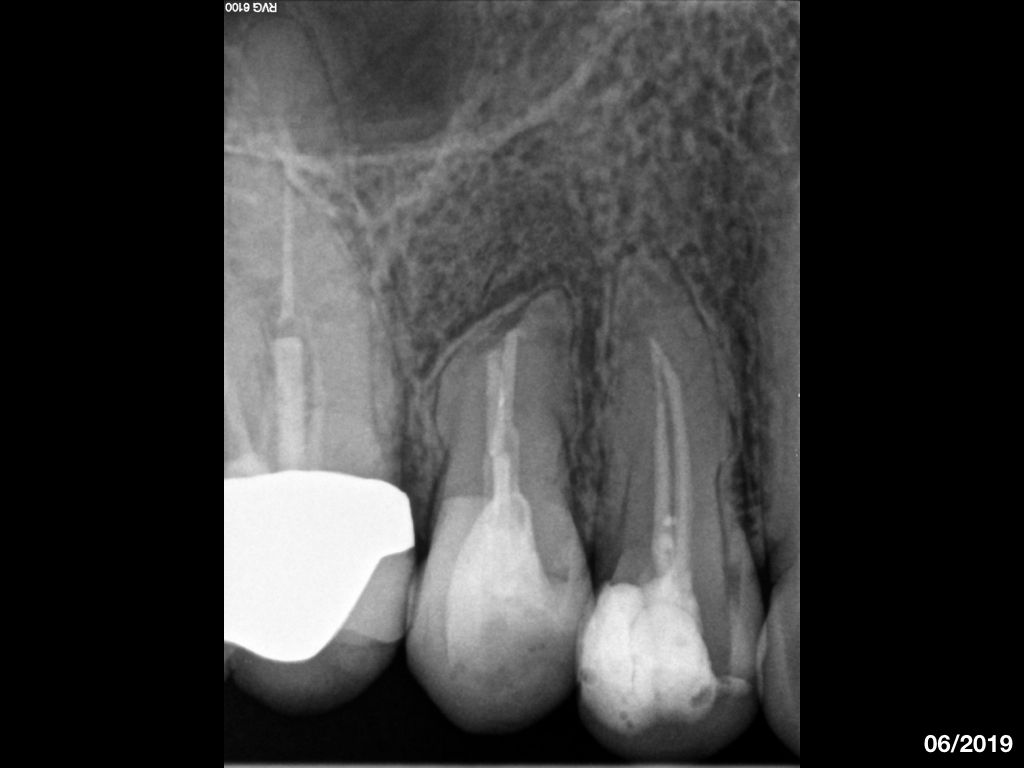

WS8593.007 Veröffentlicht 18. Juli 2019 am 1024 × 768 in Recall und Verlauf eines endodontischen Falles (2)